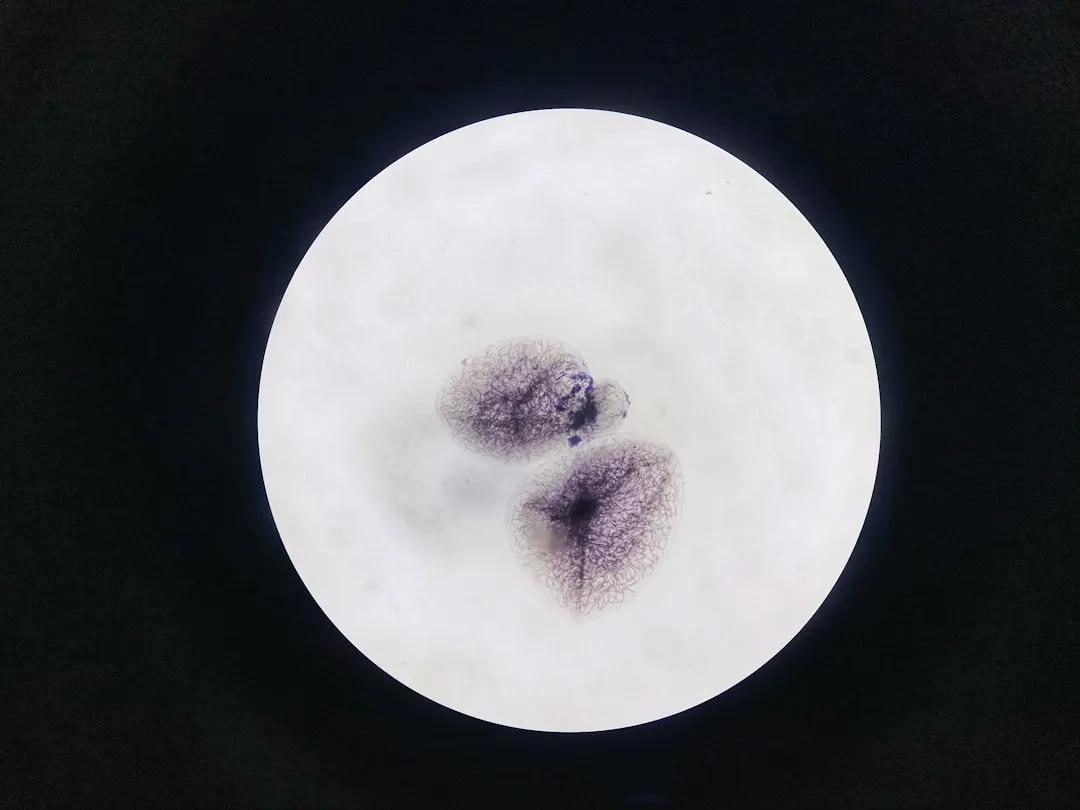

white moon on black background